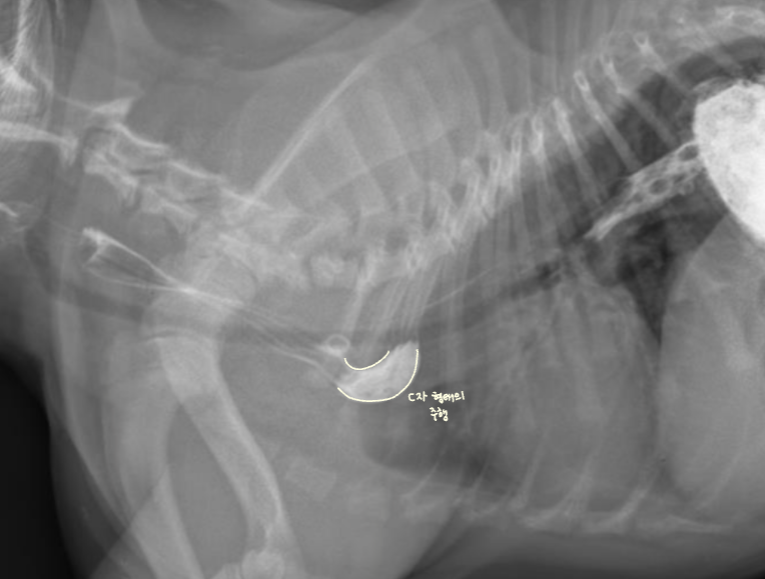

- Thoracic inlet์ ๋์ด์ ์๋์์ ์ ์์ ์ผ๋ก C์ ํํ์ ์ฃผํ์ ๋ณด์ผ ์ ์์.![]() ![]() |